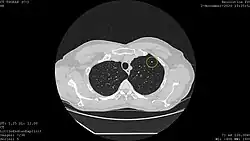

Calcified lung nodule seen on Low Dose Chest CT (circled)

Calcified lung nodule seen on Standard Dose Chest CT (circled)